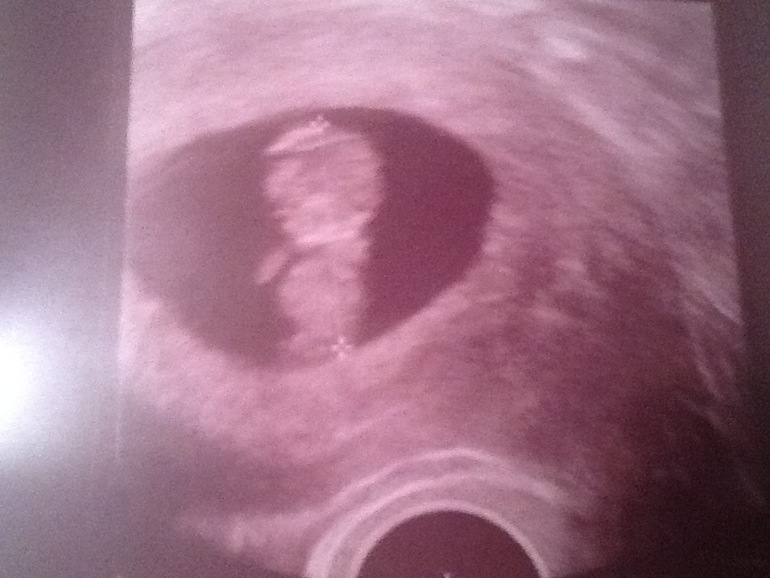

9 недель

Немного личногоСегодня была у своего любимого доктора. Отменяем часть лекарств.. Ура!!!! Из 10 останется 6. Сделали узи. Я такого восторга никогда не испытывала! Малыш танцевал , весь крутился, из 10 фото поймать удалось всего несколько! А ещё МЮЕ сказала, малыш крупный соответствует 9-10 неделькам. Теперь ждём скрининга и растём дальше!

Какая мышка тут у мамы спряталась)))))))))))) Катенька, ттт на тебя и на вас обоих)))) маленький и самый любимый)))) еще чуть чуть и шевеления начнутся)

Как здорово и какой малыш суперский! Тоже хочу на узи,но терплю до скрининга пока😉